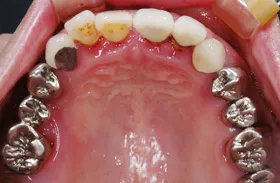

他院で「歯槽膿漏は治らない」と言われ、当院にご来院されました。歯が乱ぐいのため、歯並びもよくしたい、下は歯を既に失っているので噛めるようにもなりたい、またコーラスをされていて人前で口をあけることが多いので、できるだけ見た目を意識した治療をしてほしいとのご要望でした。

■治療前

■治療(仮歯装着)後